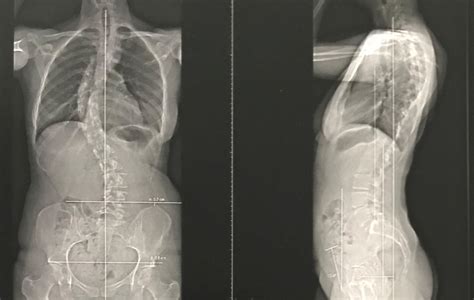

Indication et objectif de la chirurgie de la scoliose Chirurgie du dos Nice. Les fossettes du dos ou de Vénus sont ces petits trous situés dans le bas du dos Observer ces dépressions et leur état peut vous aider à mieux comprendre votre corps.